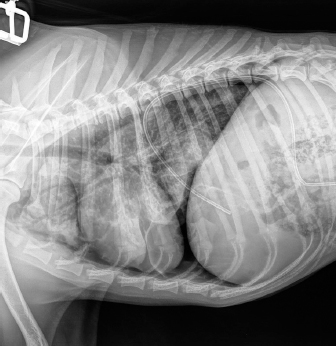

Case details for each of the five dogs included in the study are listed in Table 1. The etiology of the pneumothorax were congenital pulmonary bullae in two dogs, traumatic in one (road traffic accident), lungworm infection in one, and unknown in the remaining dog. Dog number 1 presented a large pulmonary bulla in the right cranial pulmonary lobe (Fig. 1). Dog number 2 presented four bullae: two in the medial aspect of the left cranial lung lobe (17 mm each), one in the caudal aspect of the left caudal lung lobe (26 mm), and another in the caudal border of the left caudal lung lobe (36 mm) (Fig. 2). Dog number 3 presented a large bulla measuring 33 mm in the medial aspect of the right middle lung lobe and around 10 blebs measuring from 3 to 6 mm in the ventral border of both right and left cranial lung lobes. Dog number 4 developed multiple small bullae and a larger one measuring over 10 cm, 24 hours after treatment of lungworm with spot on Imidacloprid and Moxidectin, which were responsible for a moderate unilateral pneumothorax (Fig. 3). Despite the severity of the pneumothorax, dog number 5 did not show any lesions on the computed tomography (CT) scan that could clearly explain its origin. Only one chest tube was placed in dogs 1, 2, 3, and 4. Two were placed in dog 5.

Fig. 3. Right-lateral thoracic radiograph of a 9-month-old female dog (dog number 4) suffering from a pneumothorax secondary to lungworm infection.